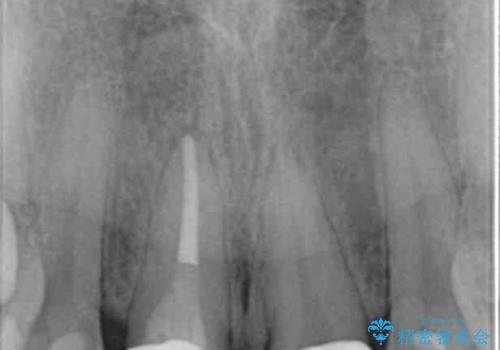

神経の治療をした歯について

神経をとる治療を行った歯は、時間が経過すると術前のように変色し見た目を大きく損ないます。

このような場合金属を使わないジルコニアクラウンを用いた治療を行うことで天然の歯のように審美性を改善することが可能になります。